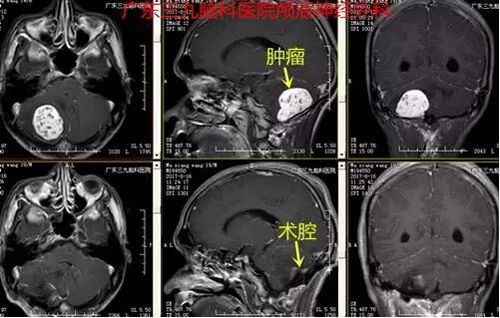

图4:术前术后MR对比提示肿瘤全切除

上述案例为实质性血管母细胞瘤,术前MR提示右侧小脑半球类圆形占位,增强明显强化,中见血管流空影,考虑血管母细胞瘤,予手术前行造影提示病变区域大片异常染色,主要由右侧脑膜后动脉、右侧椎动脉颈部分支、右侧小脑后下动脉等参与供血,予栓塞右侧椎动脉颈部分支,栓塞顺利,栓塞后造影提示肿瘤区域染色明显减少。随即送手术室行肿瘤切除,术中见右侧小脑类似血管团病变,类圆形,术中出血少,肿瘤切除时间约10分钟,手术顺利,术后患者恢复快,未有明确并发症,现恢复良好出院。